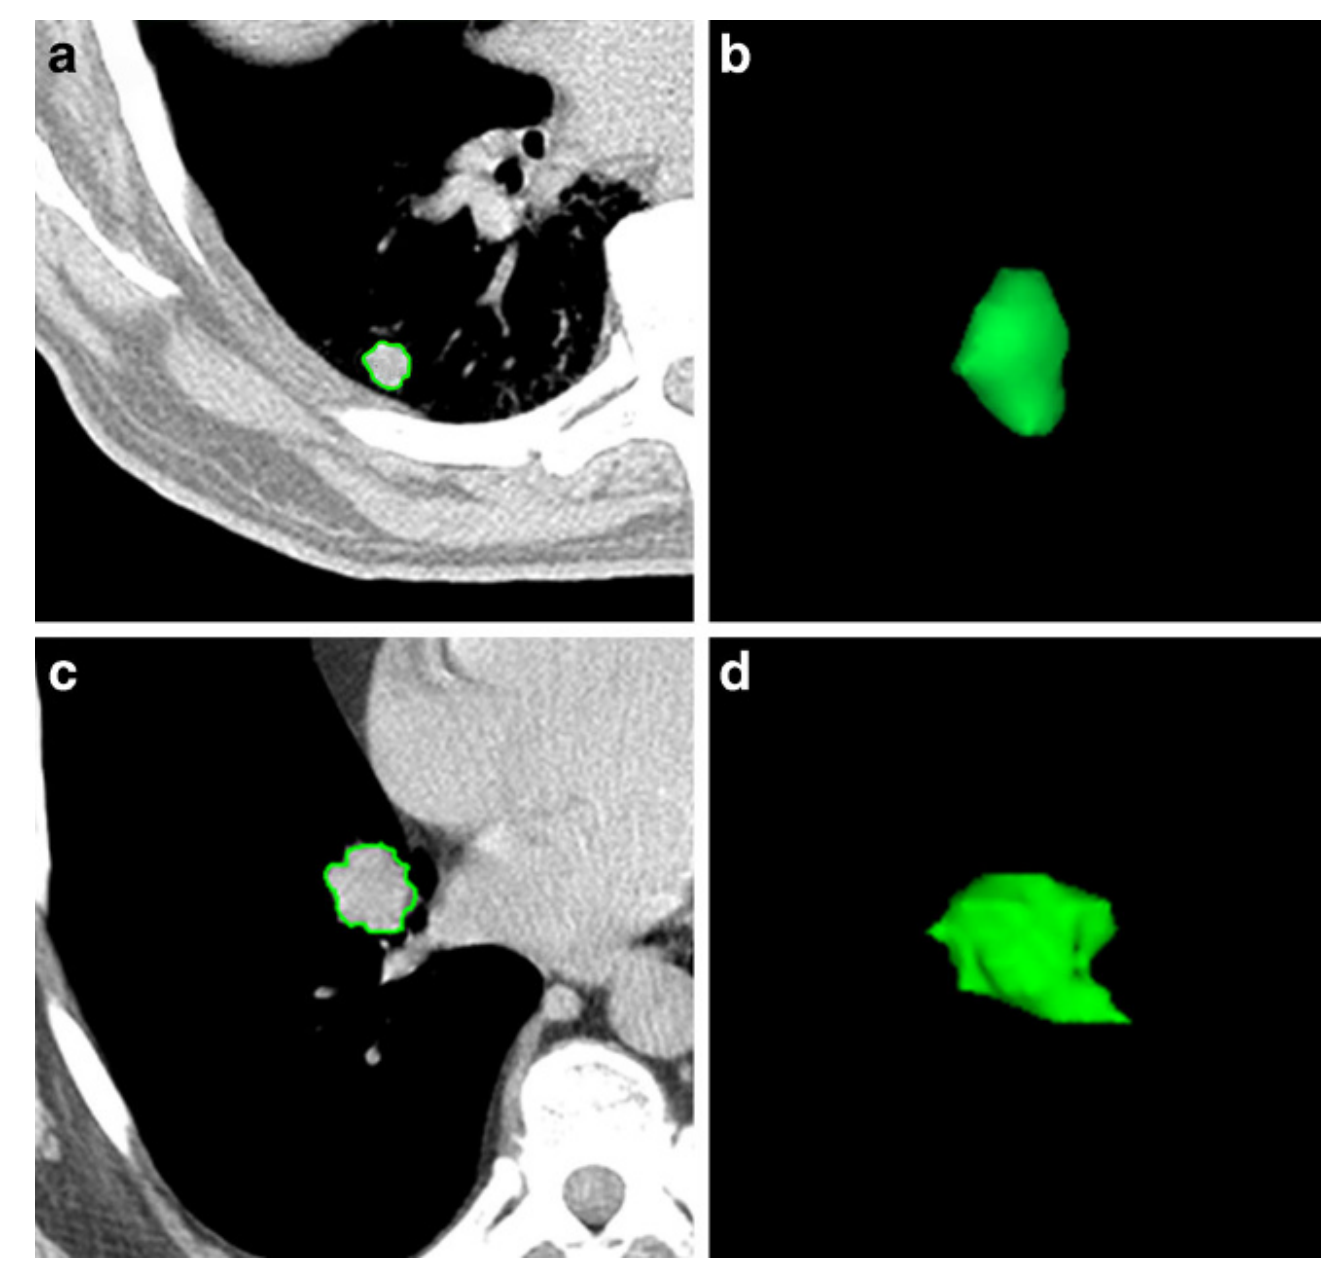

Fig. 2 展示了两个不同患者的肺部病变的轴向CT图像和3D图,以及它们的放射组学特征值。这些特征值用于区分完全缓解(CR)和疾病稳定(stable disease)的治疗结果。

以下是对图2中信息的解释

- 患者1 (a, b):

- 年龄:78岁,男性。

- 治疗结果:完全缓解(CR)。

- 患者2 (c, d):

- 年龄:75岁,男性。

- 治疗结果:疾病稳定(stable disease)。

概念解释

- 轴向CT图像:展示了病变在CT扫描中的实际图像,可以帮助观察者直观地看到病变的位置和大小。

- 3D图:通过三维重建技术,提供了病变形态的三维视图,有助于更好地理解病变的空间结构。

放射组学特征值对比

通过比较两组病变的放射组学特征,研究人员可以寻找与治疗反应相关的模式。例如,CR组的病变可能具有较高的SVR值和较低的灰度非均匀性,而疾病稳定的病变可能具有较低的SVR值和较高的灰度非均匀性。

这些观察结果可以帮助研究人员理解哪些放射组学特征可能对预测SBRT治疗的反应更有帮助。

需要注意的是,虽然图2提供了两个病变的直观比较,但为了得出统计学上显著的结论,研究人员需要分析更大样本量的病变数据,并可能使用机器学习等高级分析技术来建立预测模型。